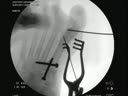

Hallux varus is a varus deformity

of the first metatarsal phalangeal joint. The lateral joint capsule is

attenuated or absent while the medial side is contracted. This deformity

can be caused by direct trauma. However, it is most often seen as an

iatrogenic (sometimes unavoidable) complication of bunion surgery where

aggressive medial eminence excision and soft tissue balancing techniques were

performed. If the condition is addressed before the onset of arthritis,

the surgeon may choose to realign the joint using capsular repair techniques

and a Mini TightRope device along the lateral collateral ligaments to support

the joint while it heals. If the joint is already arthritic, the surgeon

may choose to perform a first MTP joint arthrodesis.